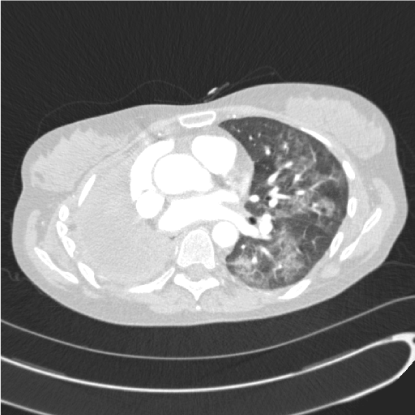

Clinical assessment revealed normal air entry on the left side of the chest with signs of a right pneumonectomy. She was tachycardic at 101 beats per minute, respiratory rate was raised at 24 per minute, oxygen saturation was reduced at 96% on 2 L/minute of oxygen. Chest radiograph demonstrated the left lung to be clear. Blood tests showed a white cell count of 14 x 109/L (normal range 4-11 x 109/L) with a neutrophilia and C reactive protein of 22 mg/L (normal range <10 mg/L). Computed tomography pulmonary angiography excluded pulmonary embolus but did show new left sided patchy and widespread ground glass changes with mediastinal lymphadenopathy (Figure 1).

Figure 1. Axial computed tomography slice of the chest showing diffuse ground glass opacification within the left lung and right pneumonectomy.